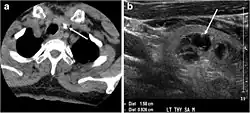

Fig. 22. A 26-year-old male patient with elevated serum parathyroid hormones and calcium secondary to intra-thyroid parathyroid adenoma. a, b Enhanced axial and coronal CT scan of the neck demonstrate a well-defined hypodense right thyroid nodule (white arrows). c Bone window coronal CT scan shows lytic expansile lesions at the right mandible and left frontal bone (white arrows). d Transverse colour Doppler ultrasound of the neck demonstrates a well-defined, heterogonous, predominantly hypoechoic right thyroid nodule measuring 2.7 cm, with mild increased vascularity and no internal micro-calcifications (white arrow). e, f Delayed anterior planar and fused SPECT/CT parathyroid Sestamibi scan at 2 hours demonstrate persistent focal activity in the right thyroid lobe (white arrows). Note the scattered mandibular/maxillary uptakes in planar image representing the known brown tumours.[1]